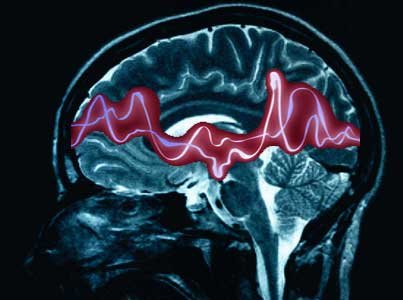

Cuando el cerebro pierde el control de sus descargas eléctricas

La epilepsia es una enfermedad neurológica crónica no transmisible que afecta a 50 millones de personas en todo el mundo. Se caracteriza por convulsiones recurrentes, que son episodios breves de movimientos involuntarios que pueden involucrar a todo el cuerpo o a una parte de él y en ocasiones se acompaña de pérdida de conciencia y del control de los esfínteres.

Las convulsiones se deben a descargas eléctricas excesivas en un grupo de células cerebrales que pueden producirse en diferentes partes del cerebro y pueden ir desde episodios muy breves de ausencia o de contracciones musculares hasta convulsiones prolongadas y graves. Su frecuencia también puede variar entre menos de una al año y varias al día.